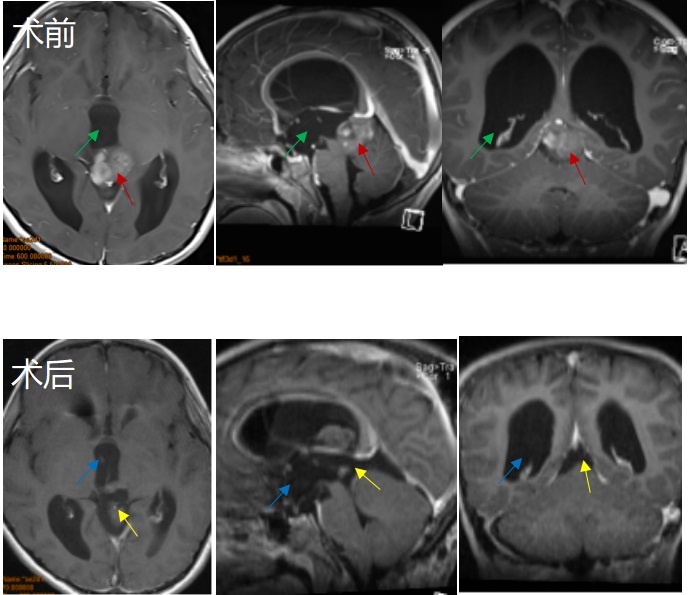

疑難松果體區(qū)腫瘤案例,INC巴特朗菲教授一次天壇醫(yī)院手術(shù)成功完成!

2023年6月,首都醫(yī)科大學(xué)附屬北京天壇醫(yī)院正式引進(jìn)INC德國巴特朗菲教授作為其神經(jīng)外科外籍專家。6月中國行中,巴教授正式以外籍專家的身份再次來到天壇醫(yī)院,走進(jìn)了天壇醫(yī)院國際部手術(shù)室...